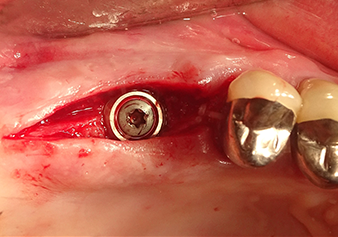

Implant bed preparation and augmentation

Following an intermediate check (Fig. 4) a further preparation step was performed (Fig. 5). Afterwards, the hydraulic Z35P instrument was used to lift the membrane to the desired position (Fig. 6 and 7). This was followed by further piezosurgical preparation of the implant bed, concluded with a rotary bur and shoulder milling cutter up to the implant diameter of 4.8 mm. Before the implant was inserted, the augmentation material (particle size approx. 0.8-1.6 mm) was introduced underneath the Schneiderian membrane (Fig. 8).

Implantation and prosthetic restoration